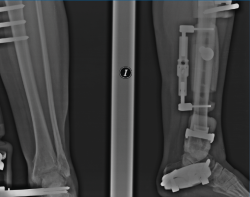

Figura 4. A y B: radiografías anteroposterior y lateral del fijador implantado con la distracción conseguida a nivel articular.